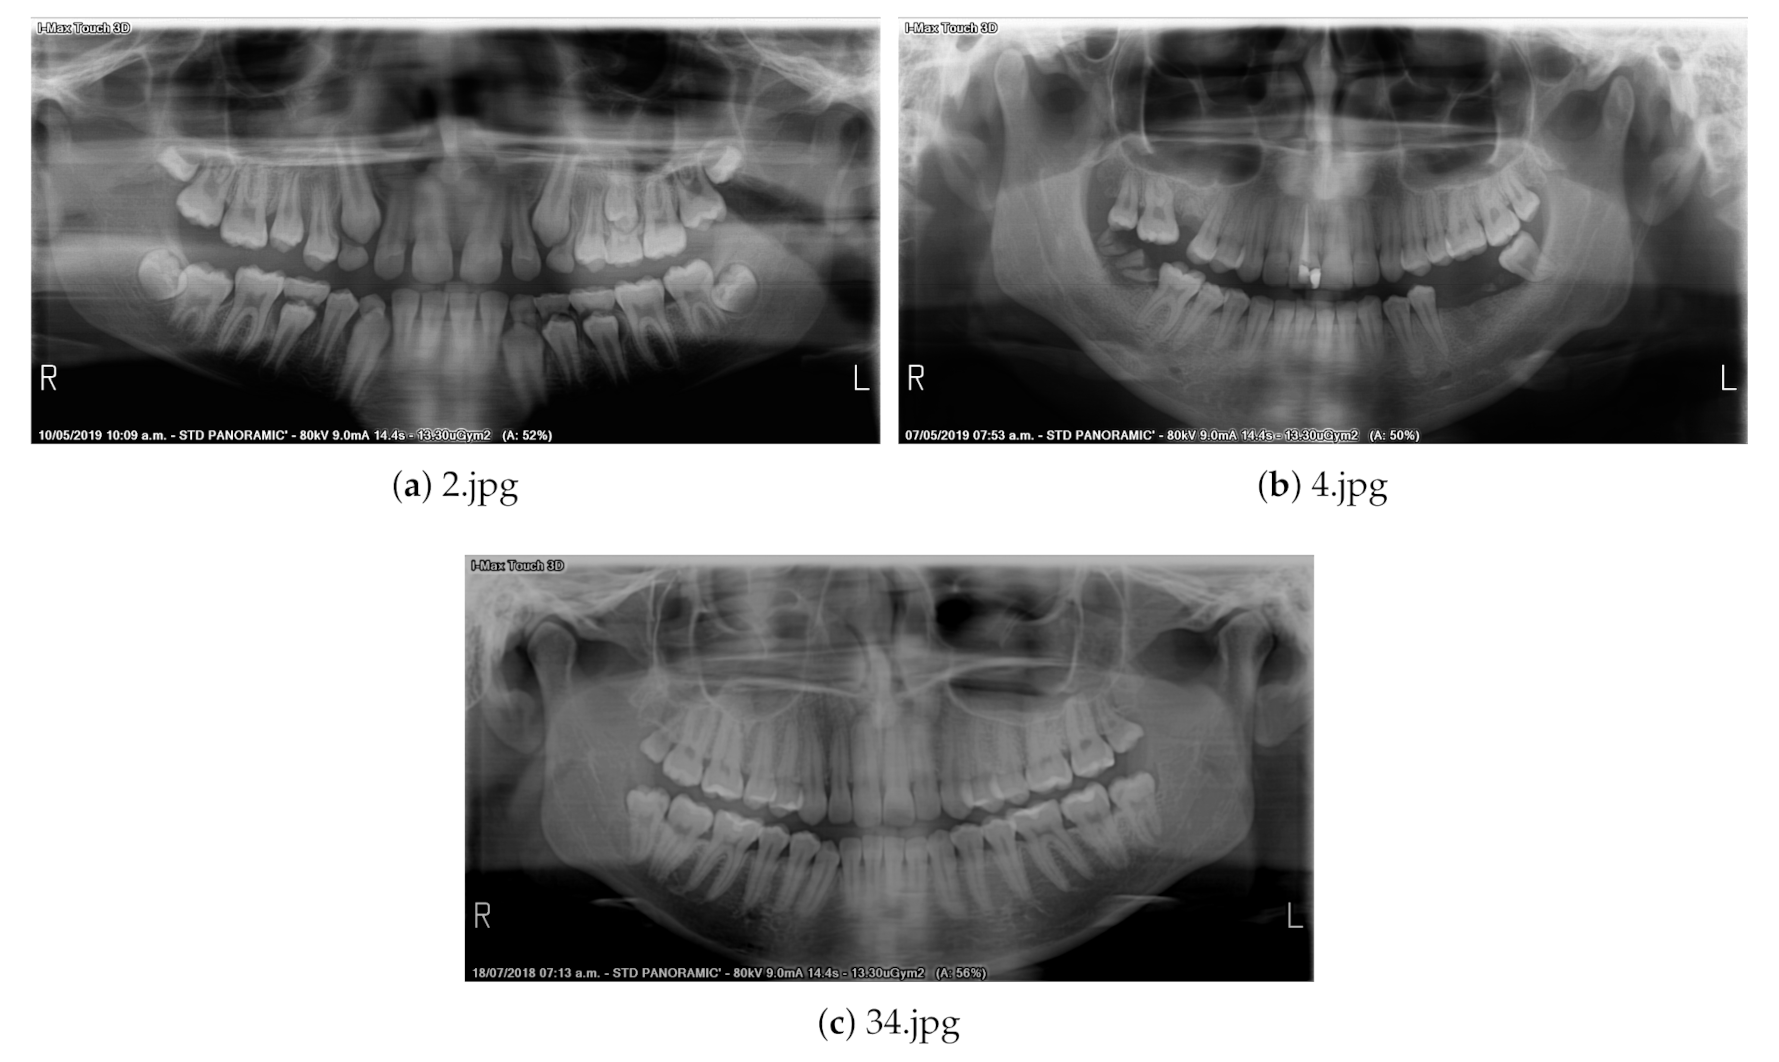

2.1. Dataset